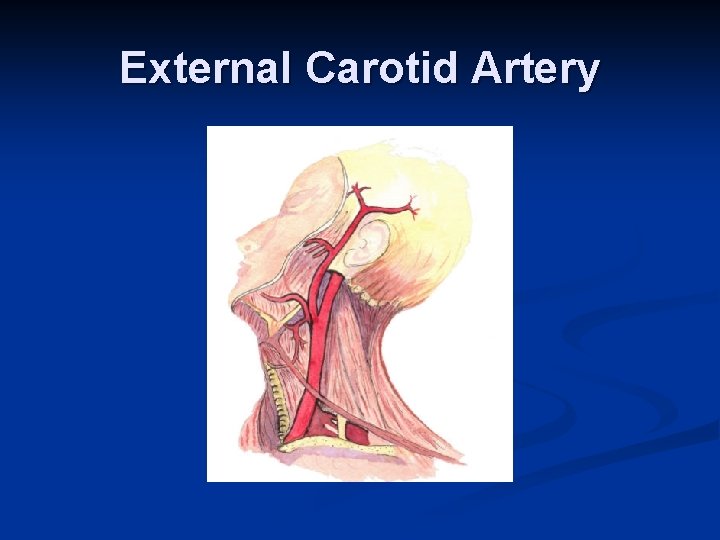

External Carotid Artery

External carotid artery. n Superior thyroidal and lingual artery branches are seen in the submandibular space. n The superficial temporal artery lies anterior to the ear.